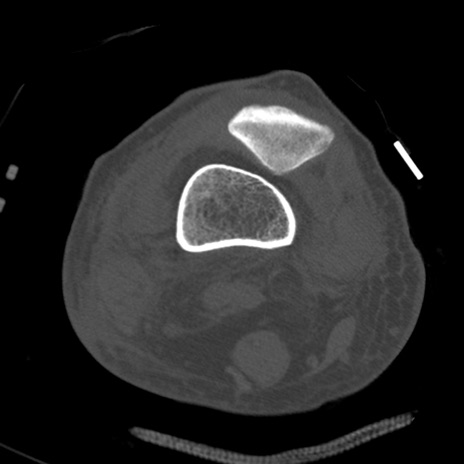

症例28 右膝関節CT(横断像)

右膝関節CT